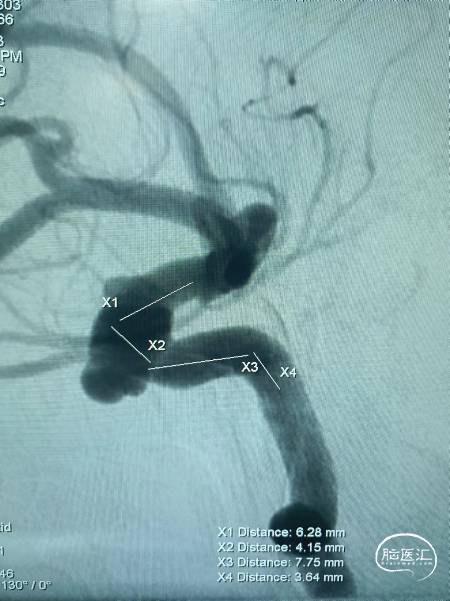

4、中间段过弯,使用推拉结合技术,确保密网支架贴壁更好。

5、近端密网支架释放:固定支架导丝,回撤微导管释放完成,不需要施加推力,XT-27微导管通过支架导丝向上跟进,旋转推挤确保密网支架贴靠更佳。

术后侧位造影